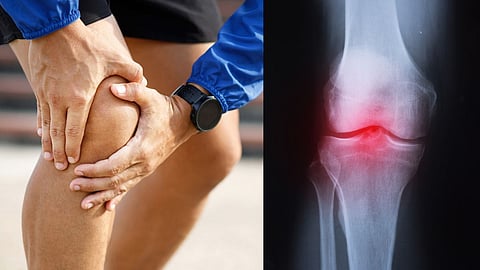

संधिवात हा एक दाहक संयुक्त विकार आहे जो सांध्याच्या ऊतींना आणि संयोजी ऊतकांना प्रभावित करतो ज्यामुळे सांधेदुखी आणि कडकपणा येतो. संधिवात 100 पेक्षा जास्त प्रकार आहेत परंतु ऑस्टियोआर्थराइटिस आणि संधिवात हे सर्वात सामान्य आहेत. संधिवात आणि संबंधित परिस्थितींनी जगभरातील अनेकांचे जीवन अपंग केले आहे.

सांधेदुखीवर कोणताही इलाज नाही आणि उपचार हा संधिवातच्या प्रकारावर अवलंबून असतो. अशा प्रकारे, लवकर निदान करण्यासाठी आणि योग्य उपचार देण्यासाठी डॉक्टर चिन्हे आणि लक्षणांच्या मदतीने वेगवेगळ्या प्रकारच्या संधिवातांचे निदान करतात.